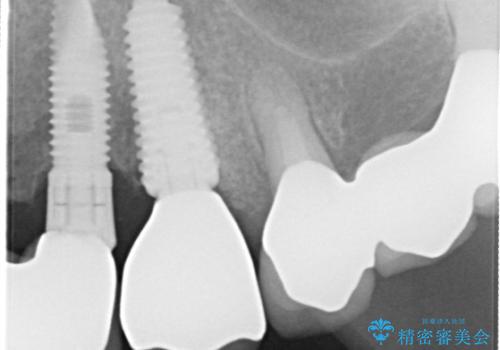

- 左上の歯肉は腫れてたまに膿が出るとの事で来院された患者様です。

検査を行い、抜歯即時インプラント(1Dayインプラント)治療を行いました。

抜歯をしインプラント埋入と骨補填材を填入して仮歯までを1日で行う「抜歯即時埋入即時過重」の手術をし、3ヶ月後には、オールセラミックを被せて定期検診となりました。